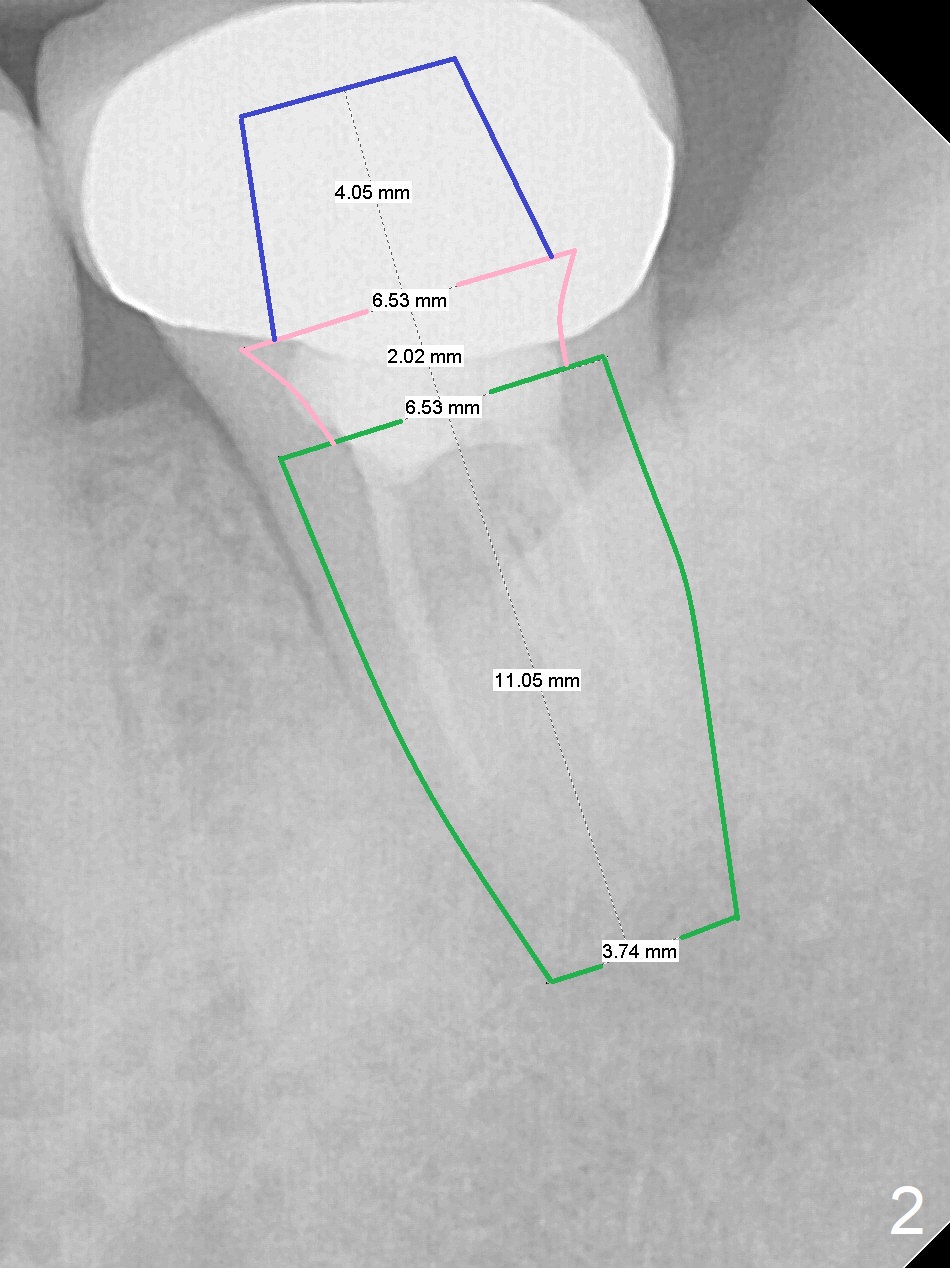

A 32-year-old woman has a buccal fistula after RCT (Fig.1). She would like to have extraction and implant to eradicate the lesion. In addition, there appear to be several canals which need to be retreated. Since the Inferior Alveolar Canal (IAC) is indistinct, osteotomy and implant placement will be confined 1-2 mm beyond the socket after debridement (Fig.2). Take the 1st intraop PA as early as possible (after use of 2 mm Bicon drill with extension and insertion of marked parallel pin). Osteotomy is buccal (if the buccal plate defect is not severe), as the IAC is lingual at this site. Also consider initiate osteotomy in the mesial slope of the socket. Prepare Sinus Master Kit for possible use of its short stoppers (2-6 mm).